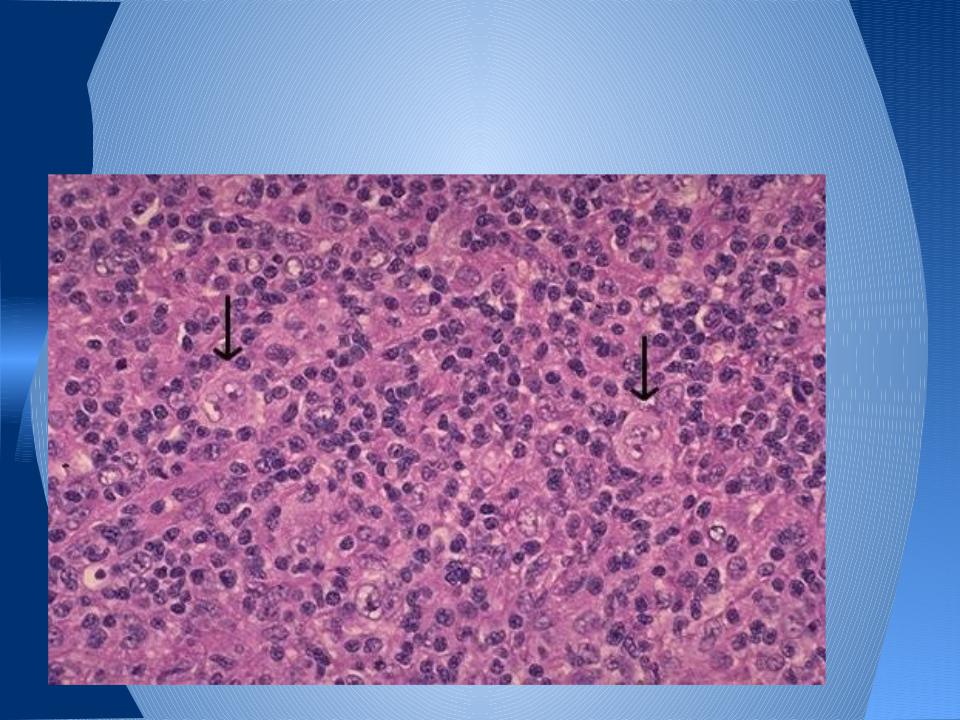

Микропрепараты: Лимфогранулематоз и Нодулярный Склероз